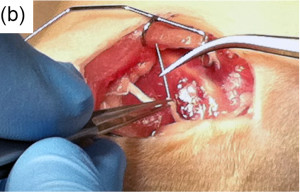

Surgery: (a) a scaffold diagram (arrows=sutures), (b) surgical pictures of the Mg insertion into nerve at surgery and (c) the PCL conduit in place.

Mg: magnesium; PCL: poly(caprolactone).2